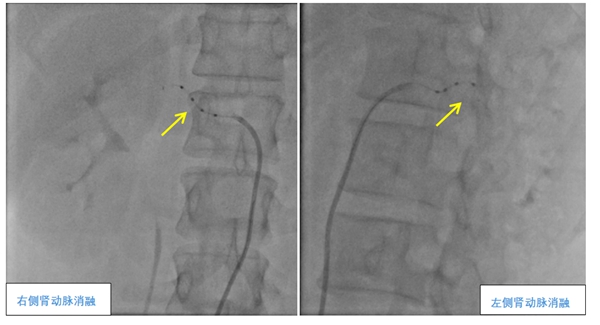

▲肾动脉去交感神经消融术(RDN)

术中,夏文豪团队对患者双侧肾动脉主干及分支进行了全面、精准的消融,共消融了38个靶点,手术仅用1小时。术后,孔女士没有任何不良反应,第二天便能下床自由活动,第三天顺利出院。在之后的多次回访中,孔女士表示她的血压已经逐渐稳定,而且头晕头痛心悸等症状明显改善。

夏文豪介绍,肾动脉去交感神经消融术是一种高血压微创介入手术,通过消融肾动脉周围的交感神经,降低其兴奋性,从而达到长效降压的效果。目前中山一医广西医院心血管内科团队在这一项全新领域中有着丰富的经验,已成功完成11例,指导桂林人民医院、桂林医学院第二附属医院、柳州工人医院、揭阳市人民医院等完成5例,为多位不同情况的患者成功控制住了高血压。